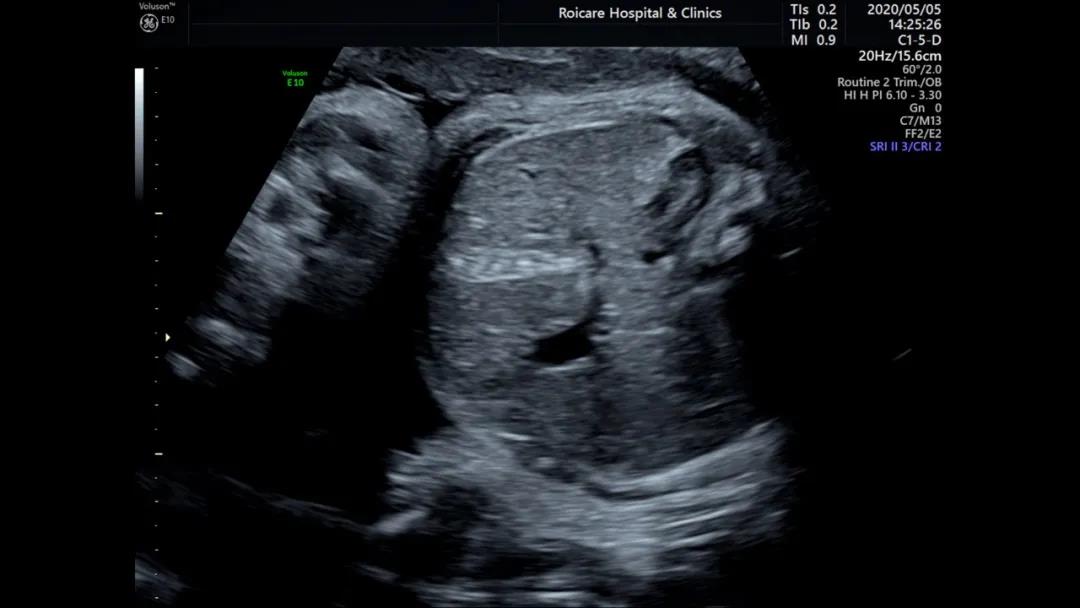

3.肠管强回声

肠管回声增强,往往不像心室强光点那么简单,如果是因胎粪滞留导致的,这种生理性的回声增强往往会是一过性的,复查后会消失。而肠管回声增强持续存在的时候,很可能是很多异常的早期提示, 包括染色体异常、肠道的梗阻、胎儿腹膜炎、胎儿宫内感染、囊性纤维化等。

所以超声提示肠管回声增强时,宝妈需要找到产前诊断的医生进行咨询,切记莫要盲目乐观。